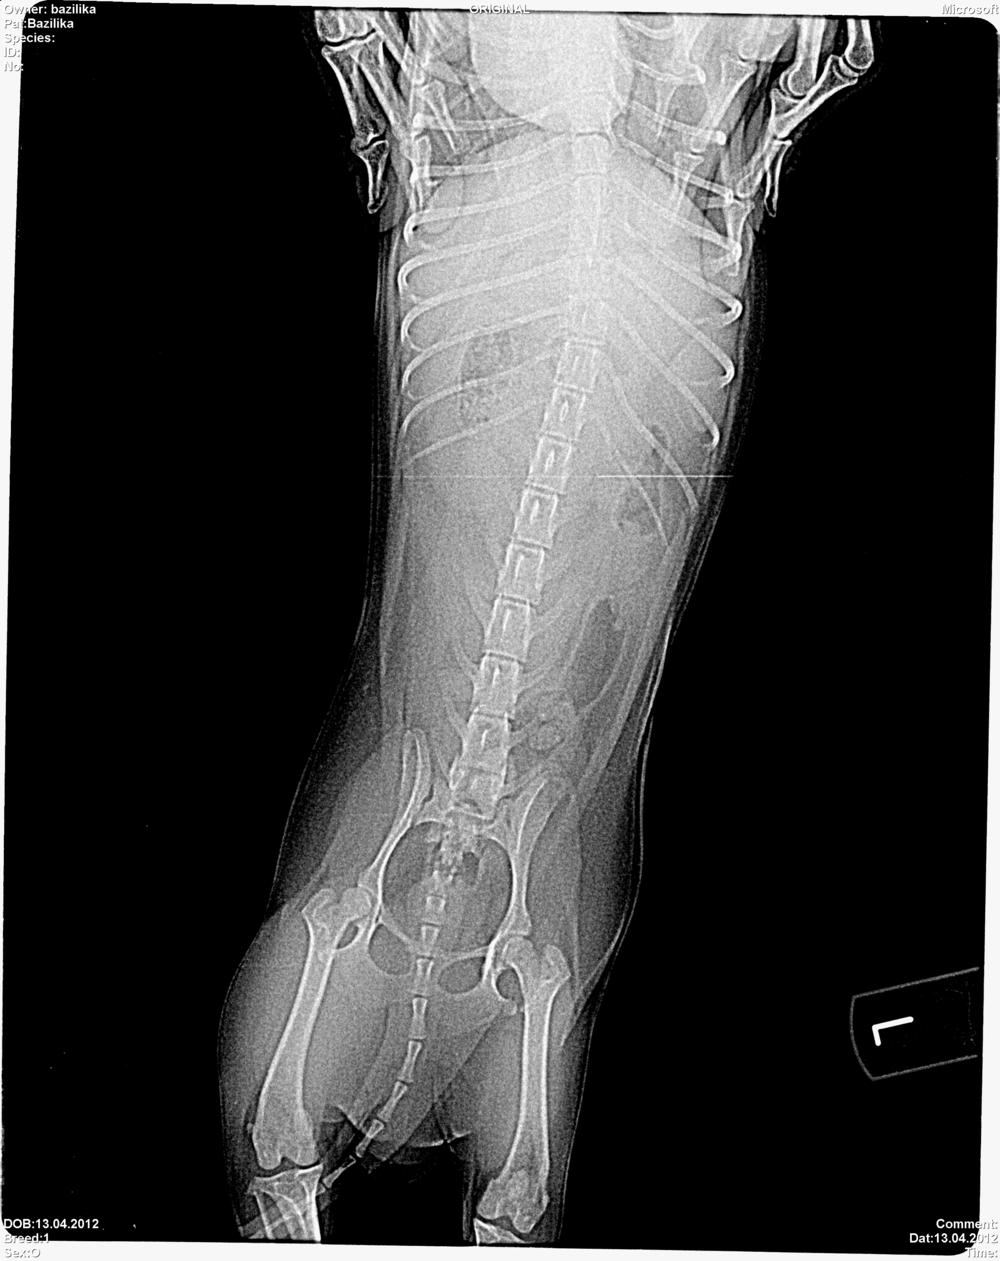

Насколько я поняла одна косточка перестала расти(закрылась зона роста),а вторая растет и изгибается(синдром лука)! Это проблема сустава ?Может мы перерастем на хондропротекторах?:cry:

Здравствуйте! Нужен Ваш совет. У меня девочка чихуахуа,7,5 месяцев. Начала поджимать заднюю левую лапку. Несколько дней поджимала и даже не наступала на нее. Сегодня были на приеме у Емельянова В.В. в Первомайском ветцентре. Девочку осмотрел,направил на рентген и поставил диагноз "Вывих коленной чашечки левой тазовой конечности" . Сказал нужна операция. Больше ничего не назначил. У нас сейчас первая течка. По окончании течки сказал надо оперироваться. Попробую вставить снимок, посмотрите,может можно попробовать подавать страйд. Очень не хочется под нож.